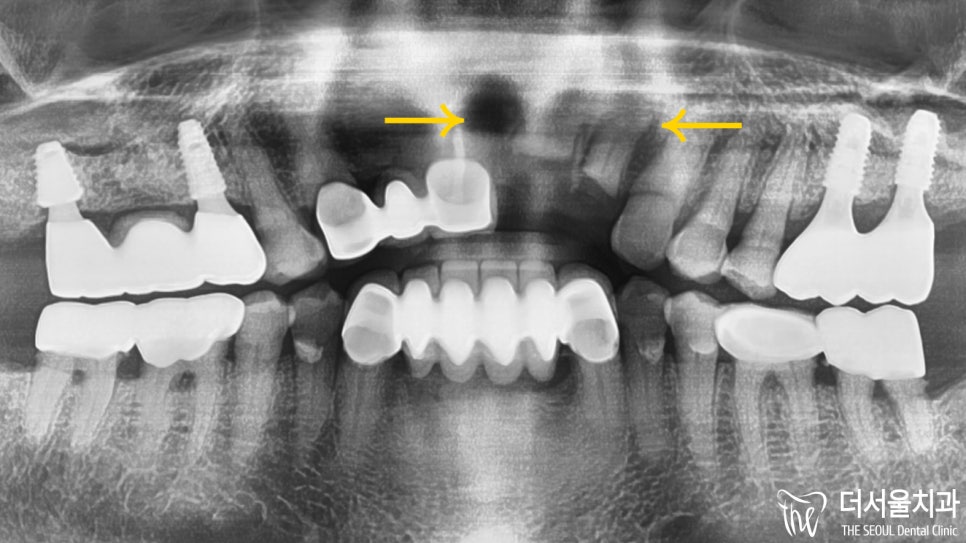

아무래도 단순히 부러진 것이 아니라는 판단이 들어

정확한 진단을 위해 엑스레이 촬영을 진행했습니다.

그 결과.. 뼈까지 손상이 생겨있는 것을 확인할 수 있었죠.

아.. 이런 경우에는 치아만 뺀다고 해서 될 문제가 아닙니다.

단순히 치아만 파절 되었다면 비교적 간단하게 해결할 수 있지만

이렇게 뼈에도 문제가 생긴 경우에는 그렇지 못하죠..

치조골 소실도 심한 상태였기에

더서울에서는 뼈이식을 동반한 임플란트 로

치아 부러짐 및 상황이 좋지 않은 송곳니까지

개선을 도와드리기로 했습니다.